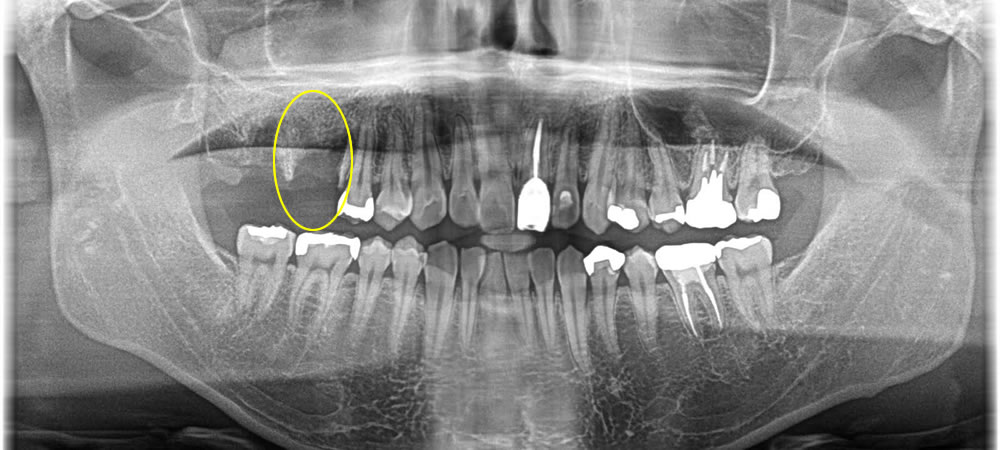

他院で抜歯した部分をインプラントで治療した症例

こちらの患者さまは、他院にて歯を抜いて歯が無くなっている所にインプラント治療を行いたいとの事で来院されました。

まずは割れた歯の根が残っていたので除去した後、中の膿が溜まっている所を綺麗にし即時でインプラントを埋入、骨を作る処置までを行いました。

ほっぺた側の骨が無くなっていましたが、しっかりと骨を作る事で歯茎の下がりを最小限に抑えることができました。